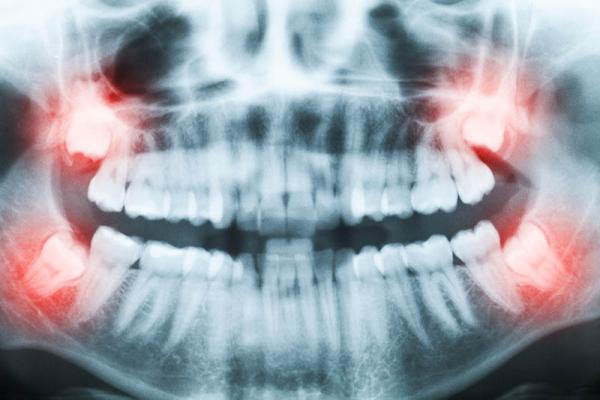

A hagyományos fogorvosi ellátáson túl vannak olyan sürgősségi, illetve előre tervezhető esetek, amelyeknél már konkrét szájsebészeti beavatkozásra van szükség. A műtét ilyenkor nemcsak a fogakat, hanem az arcot, arcüreget, esetleg az alsó és felső állcsontokat is érintheti. Vagyis itt olyan sebészeti beavatkozásról van szó, amelyet csak szájsebész szakorvos végezhet és a fogszabályozás, valamint a fogpótlások és a szájüregben lévő egyéb fogászati problémák sikeres kezeléséhez kapcsolódik.

A szájsebészet területéhez tartozó leggyakoribb beavatkozások fogászati rendelőnkben:

• bonyolultabb foghúzás

• bölcsességfog eltávolítás

• foggyökér eltávolítás

• ciszta eltávolítás

• gyökércsúcs rezekció

• arcüreg zárás

• nyálkahártya és ínykorrekció

• csontpótló műtétek (pl. arcüreg emelés)

• implantátumok beültetése